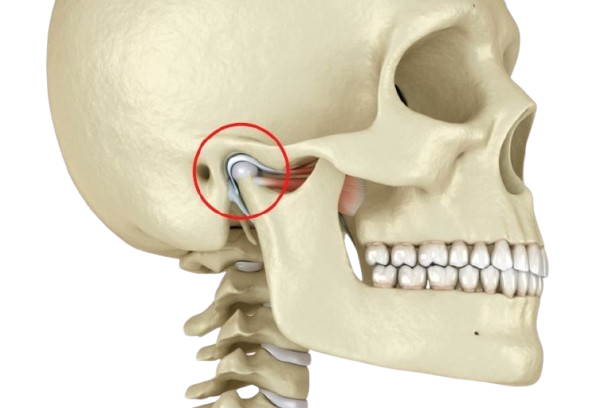

Mi enfoque se basa en comprender la etiología de cada caso, priorizando la salud articular, el desarrollo en pacientes en crecimiento y una atención integral. Aspiro a ofrecer una ortodoncia diferente: fundamentada, personalizada y con impacto duradero en la calidad de vida del paciente.